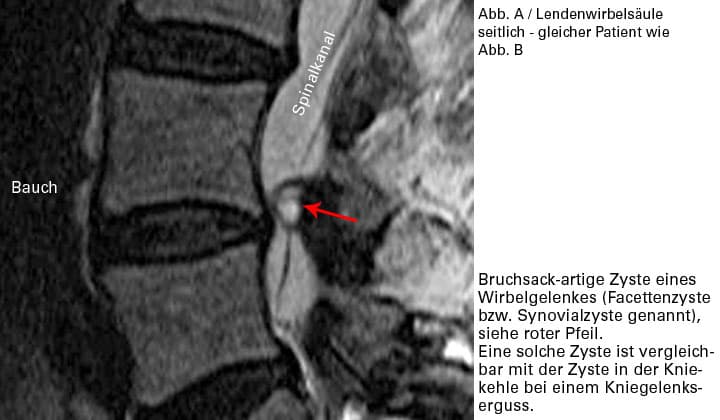

In extrem seltenen Fällen kann ein Gelenkerguss zu einer Schleimhaut-Cyste führen, die wie ein BSV eine Nervenwurzelquetschung verursachen kann.